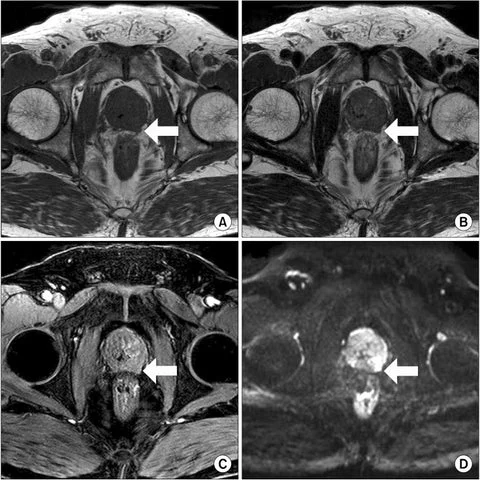

Posteriormente, em seu segundo estágio de ação, ele atua na normalização do tamanho da próstata e na eliminando a hiperplasia prostática benigna (HPB) e a prostatite.